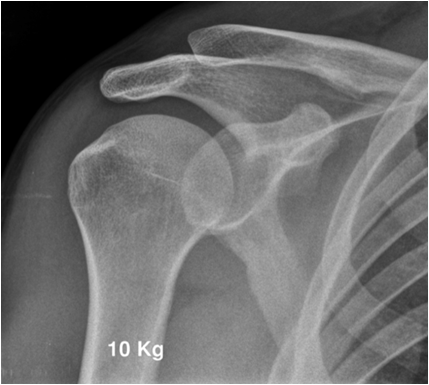

Joint relationships can frequently be evaluated better with the aid of stress films. Stress may be applied either by weight bearing (evaluation of the acromioclavicular joint) or by external stress applied to alter the at-rest relationship (evaluation of ankle ligaments). Stress films are used to test joint stability in suspected ligament injury. Images are taken under defined conditions with weight or pressure applied. Subluxation or joint space widening indicates partial or complete rupture of the ligaments tested. Before ordering stress images a set of conventional images in mandatory to exclude fracture.

Fig. 4. Stress test of acromiclavicular joint instability. The patient is holding 10 kg weight in each hand. Note the step in the right acromiclavicular joint indicating injury to the ACG capsule and the coracoclavicular ligament.